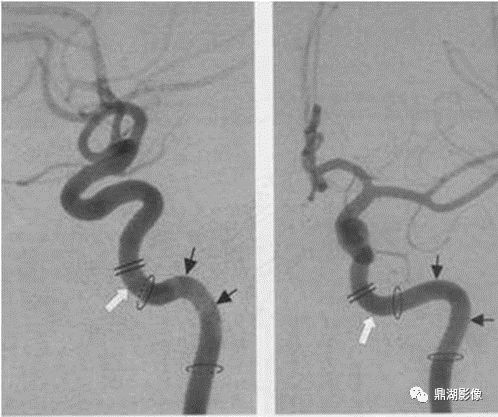

完整汇总 | 颈部及颅内动脉影像分段

各种颅内出血

几种类型脑出血的CT表现